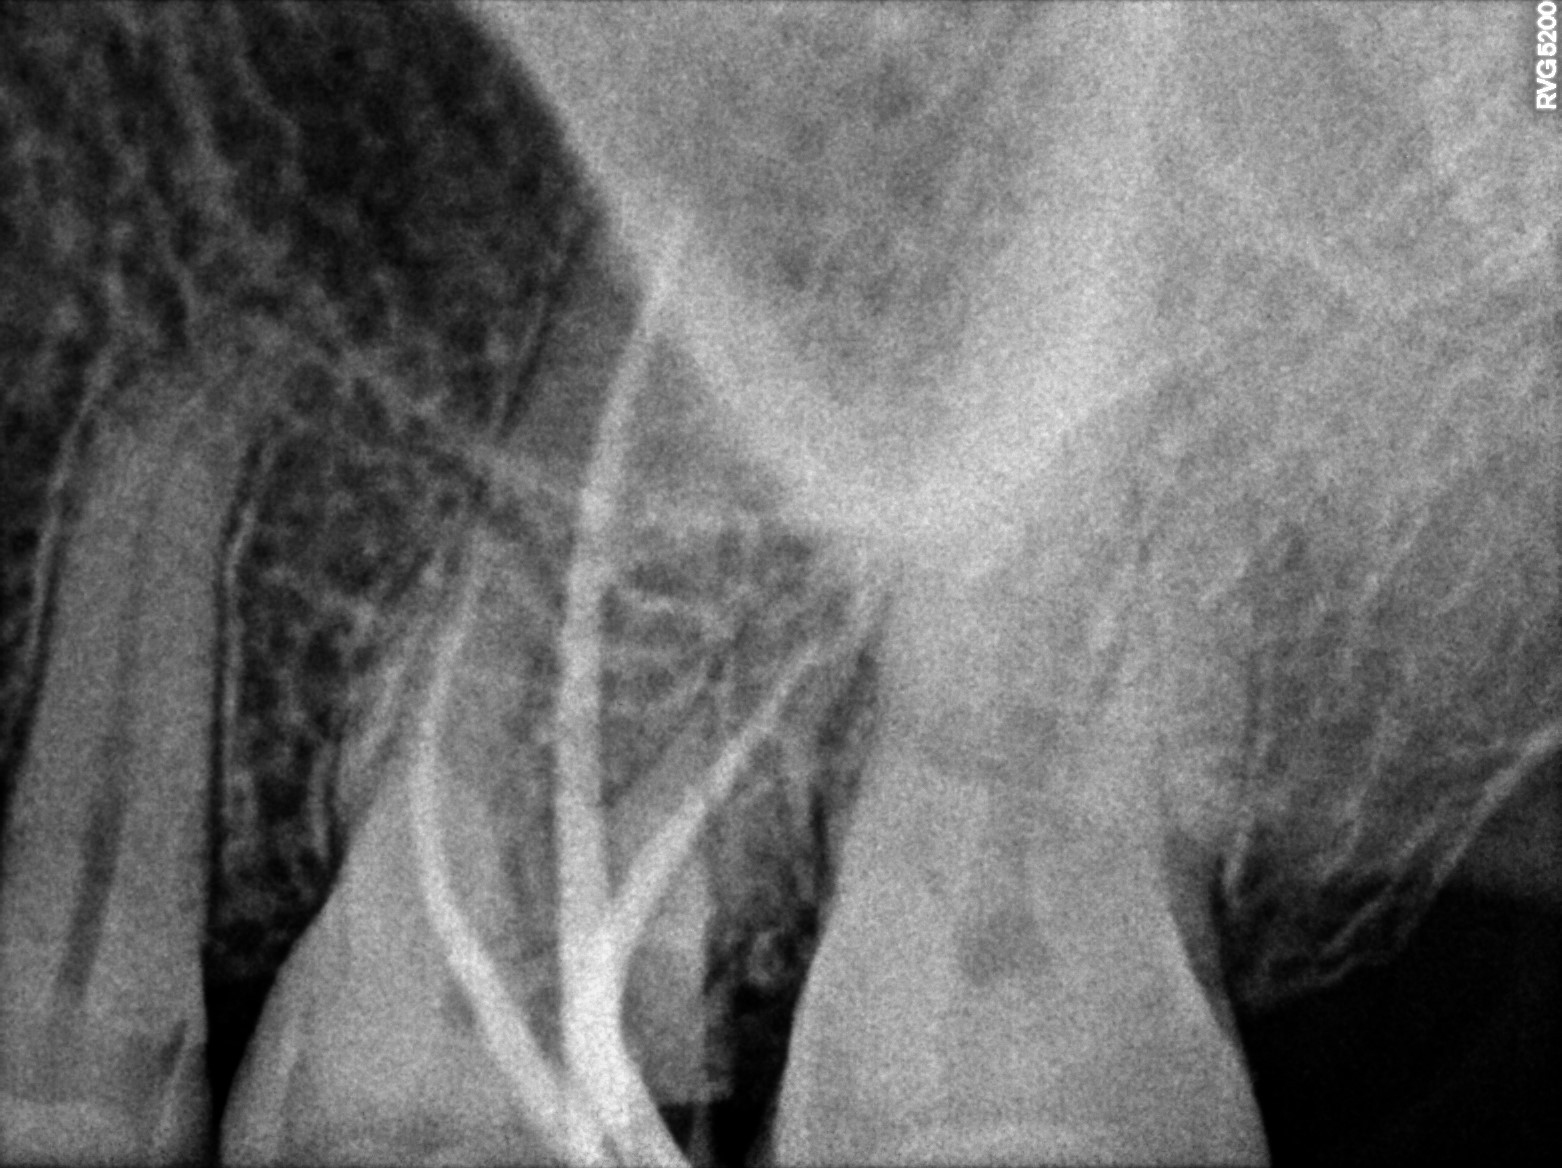

Dental Radiographs FHIR: DocumentReference · LOINC 24641-7

R38.jpg

24641-7